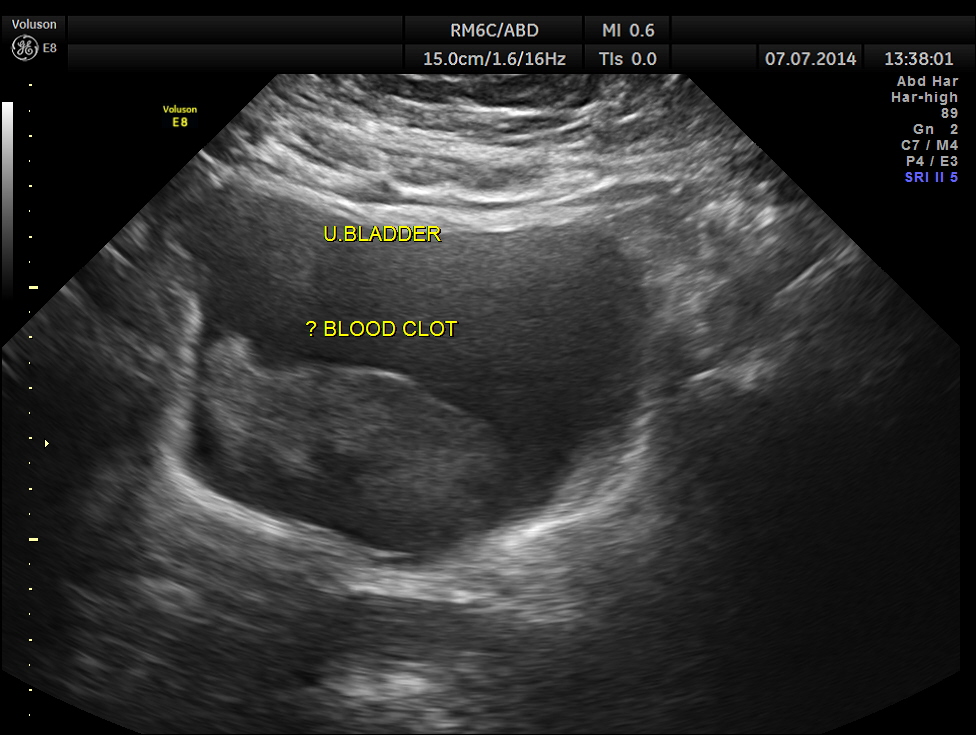

His ultrasound showed the following :

The urinary bladder showed ? mass lesion at first look.

With change of position this ” mass ” was seen to roll within the urinary bladder , suggestive of blood clot.

In this patient the increased vascularity is brought out very well by glass body imaging . Clots of blood seen in the urinary bladder gave the false impression of a mass lesion in the bladder initially.The importance of a dynamic study of turning the patient to the sides should always be remembered.